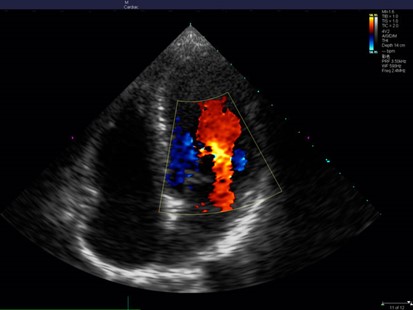

Simple, rebotando las ondas contra el fluido, logra medir la velocidad con la que esta se acerca (color rojo en Doppler color) o se aleja (azul) al transductor.

El Doppler color que nos muestra los flujos, donde un ojo con poco entrenamiento puede visualizar movimientos anormales. Este solo muestra color, no entrega ondas. Para hacer cálculos se requiere utilizar algunas de los otros 2 modos.